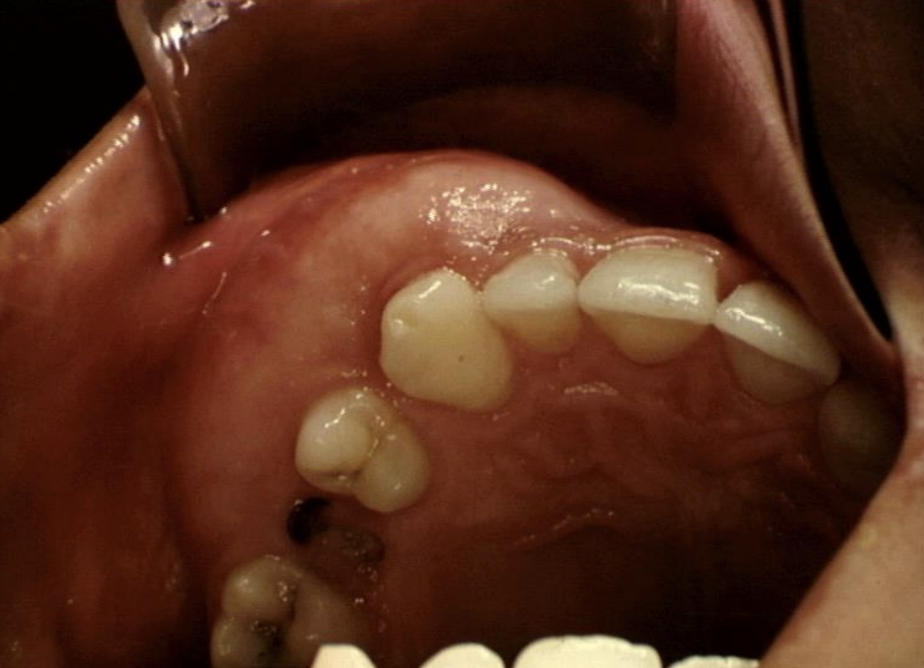

What pathology is seen in this photo?

A

Fibrous dysplasia?